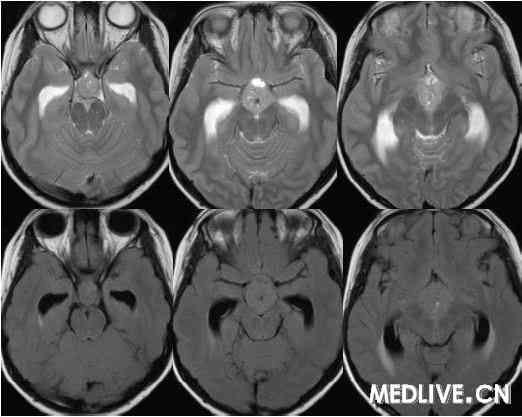

经典病例: 男性,15岁,身材发育迟缓,多饮多尿3年身材矮小

男性,15岁,身材发育迟缓,多饮多尿3年身材矮小 病理症阴性

鞍区生殖细胞瘤临床症状:多饮多尿,视力障碍 身材矮小,性早熟。

解答详情: 生殖细胞瘤由原始的生殖细胞衍生而来,好发于松果体区,其次为鞍上池。肿瘤多发生于男性青少年,位于鞍上生殖细胞瘤则以女性多见。生殖细胞瘤对放射线非常敏感。该瘤通常无包膜、无钙化、出血、坏死或囊性变,属低度恶性肿瘤,多呈浸润性生长,常有不同程度和形式的转移,易向蛛网膜下腔及脑室系统种植、播散。组织学上,肿瘤主要含有两种细胞成分:上皮样细胞和淋巴样细胞。 1、CT表现:  ①肿瘤最常见于松果体区,位于鞍上区肿块常累及漏斗;  ②CT平扫多呈等密度或稍高密度肿块,无出血、坏死及囊性变,可分叶,但境界清楚;瘤体本身钙化少见,典型松果体区生殖细胞瘤常见肿瘤包埋松果体钙化灶。  ③增强扫描呈中等至明显的均匀强化。  ④室管膜下转移可表现为沿脑室壁线状或条片状强化,沿脑脊液向蛛网膜下腔播散表现为脑表面、脑池的线状或结节状强化。   2、MR表现:  ①最常见于松果体区,也常见于鞍上,可同时或单独存在。②T1加权为略低信号或等信号,T2加权常呈等信号或高信号。③增强后;呈明显均匀一致强化,并能发现沿脑脊液或室管膜转移的病灶。鉴别诊断  1、颅咽管瘤:多为囊性或囊实性肿块,钙化多见。纯实性者可呈稍高密度,并可强化,与生殖细胞瘤不易鉴别、  2、星形细胞瘤:一般肿瘤较大,密度偏低,后期可出血,肿瘤通常位于下丘脑,并沿视交叉或视束延伸,可在眼眶内形成肿块。  3、垂体瘤:发生于鞍内,但可向鞍上生长,小儿罕见,肿瘤易出血、坏死,鞍底骨质变薄、下陷,海绵窦常受累。 生殖细胞瘤。4、脑膜瘤:好发于成人,儿童罕见,肿瘤部位偏前,伴骨质增生、硬化及蝶窦过度气化。